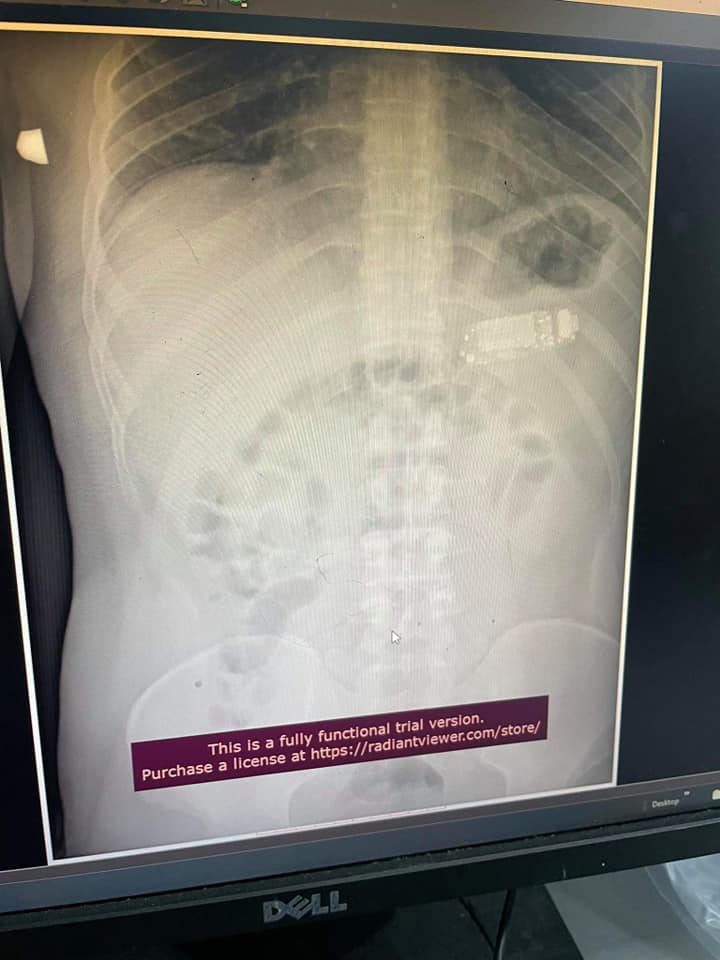

Врачи в Косово извлекли мобильный телефон из желудка 33-летнего мужчины, через 4 дня после его проглатывания. Мужчина обратился в больницу в Приштине из-за боли в животе.

Гаджет оказался слишком большим, чтобы пациент мог его переварить. Угрозу для жизни мужчины создавала коррозионная кислота из аккумулятора, которая могла вытечь наружу.

Доктору Скендеру Теляку удалось извлечь из живота пациента инородный предмет, не разрезая желудок. Для этого был использован эндоскоп.

Предполагается, что это L8STAR BM90, модель, которая внешне напоминает Nokia 3310, но имеет меньший размер.